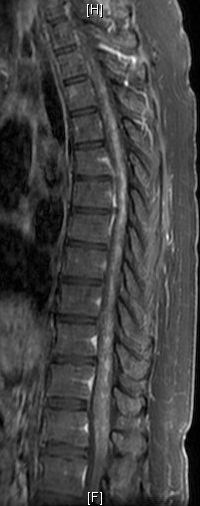

CLIPPERS综合征全称“类固醇激素反应性慢性淋巴细胞性炎症伴脑桥血管周围强化症”,是指在脑桥、中脑及小脑血管周围以淋巴细胞浸润为主、对类固醇激素治疗有效的慢性炎性疾病。该综合征由Pittock等于2010年首次报道,目前世界各地共报道100多例,国内报道不超过20例。其典型的头颅MRI增强检查示脑桥血管周围呈“胡椒粉”样斑点状强化病灶。本例患者MRI图像,与经典的CLIPPERS综合征影像不符合,强化灶并非以脑桥最密集,而是脊髓更显著,并且累及脊髓全长达腰膨大,双侧基底节脑室旁多发病灶,而且患者颅内受损的症状并不明显,这与文献报道的典型的CLIPPERS综合征并不符合。

治疗前                         治疗后

本例患者颅内病灶散发,脑活检的成功率可能不高,神经中心武剑主任和王贵怀主任对患者进行了详细的评估,经与患者家属充分沟通后,成功对该例患者进行了脊髓活检,手术顺利完成,术后患者无不适反应,病理结果回报符合典型的CLIPPERS综合征的表现,可除外脊髓结核、肿瘤等。至此该患者诊断CLIPPERS综合征明确,给与足量的激素冲击治疗后患者的临床症状明显缓解,复查MRI提示颅脑和全脊髓异常强化病变明显减少,并且强化程度减低,患者可独自站立,脊髓活检处手术切口愈合好。目前患者仍在密切门诊随访中。